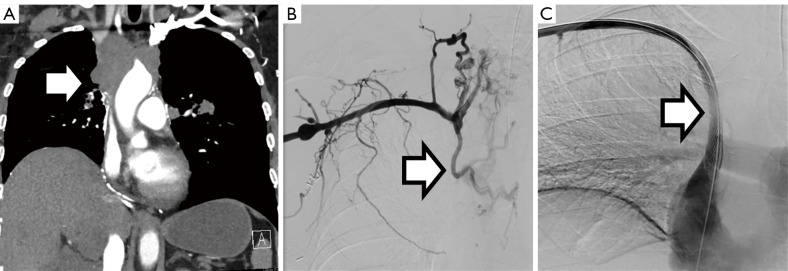

Abstract Image